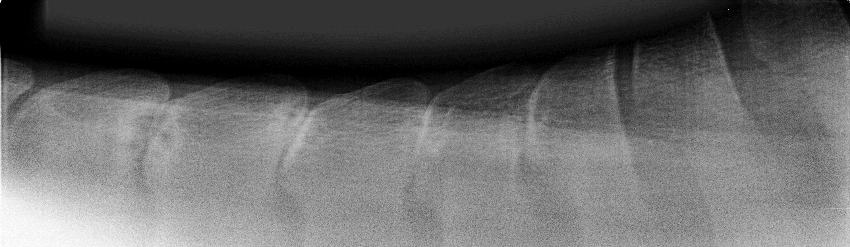

Afb. 1: Een normale rug

Afb. 2: Kissing spines

Door middel van röntgenfoto’s (foto’s hierboven) kunnen de benige structuren van de rug beoordeeld worden. Bij kissing spines zie je op de foto dat de spinaaluitsteeksels te dicht bij elkaar staan. Je kunt vaststellen op welke en hoeveel plaatsen de ruimte tussen de spinaaluitsteeksels te nauw of afwezig is. Je ziet botnieuwvorming als wittere gebieden op de foto en botverval als donkerdere ‘holtes’. De rug bestaat naast botten ook uit weke delen; spieren en banden (ligamenten). Deze kunnen met behulp van echografie beoordeeld worden. De echo kan gebruikt worden om de ernst van de kissing spines en ligamentschade vast te stellen.

Afb. 3: Ernstige kissing spines